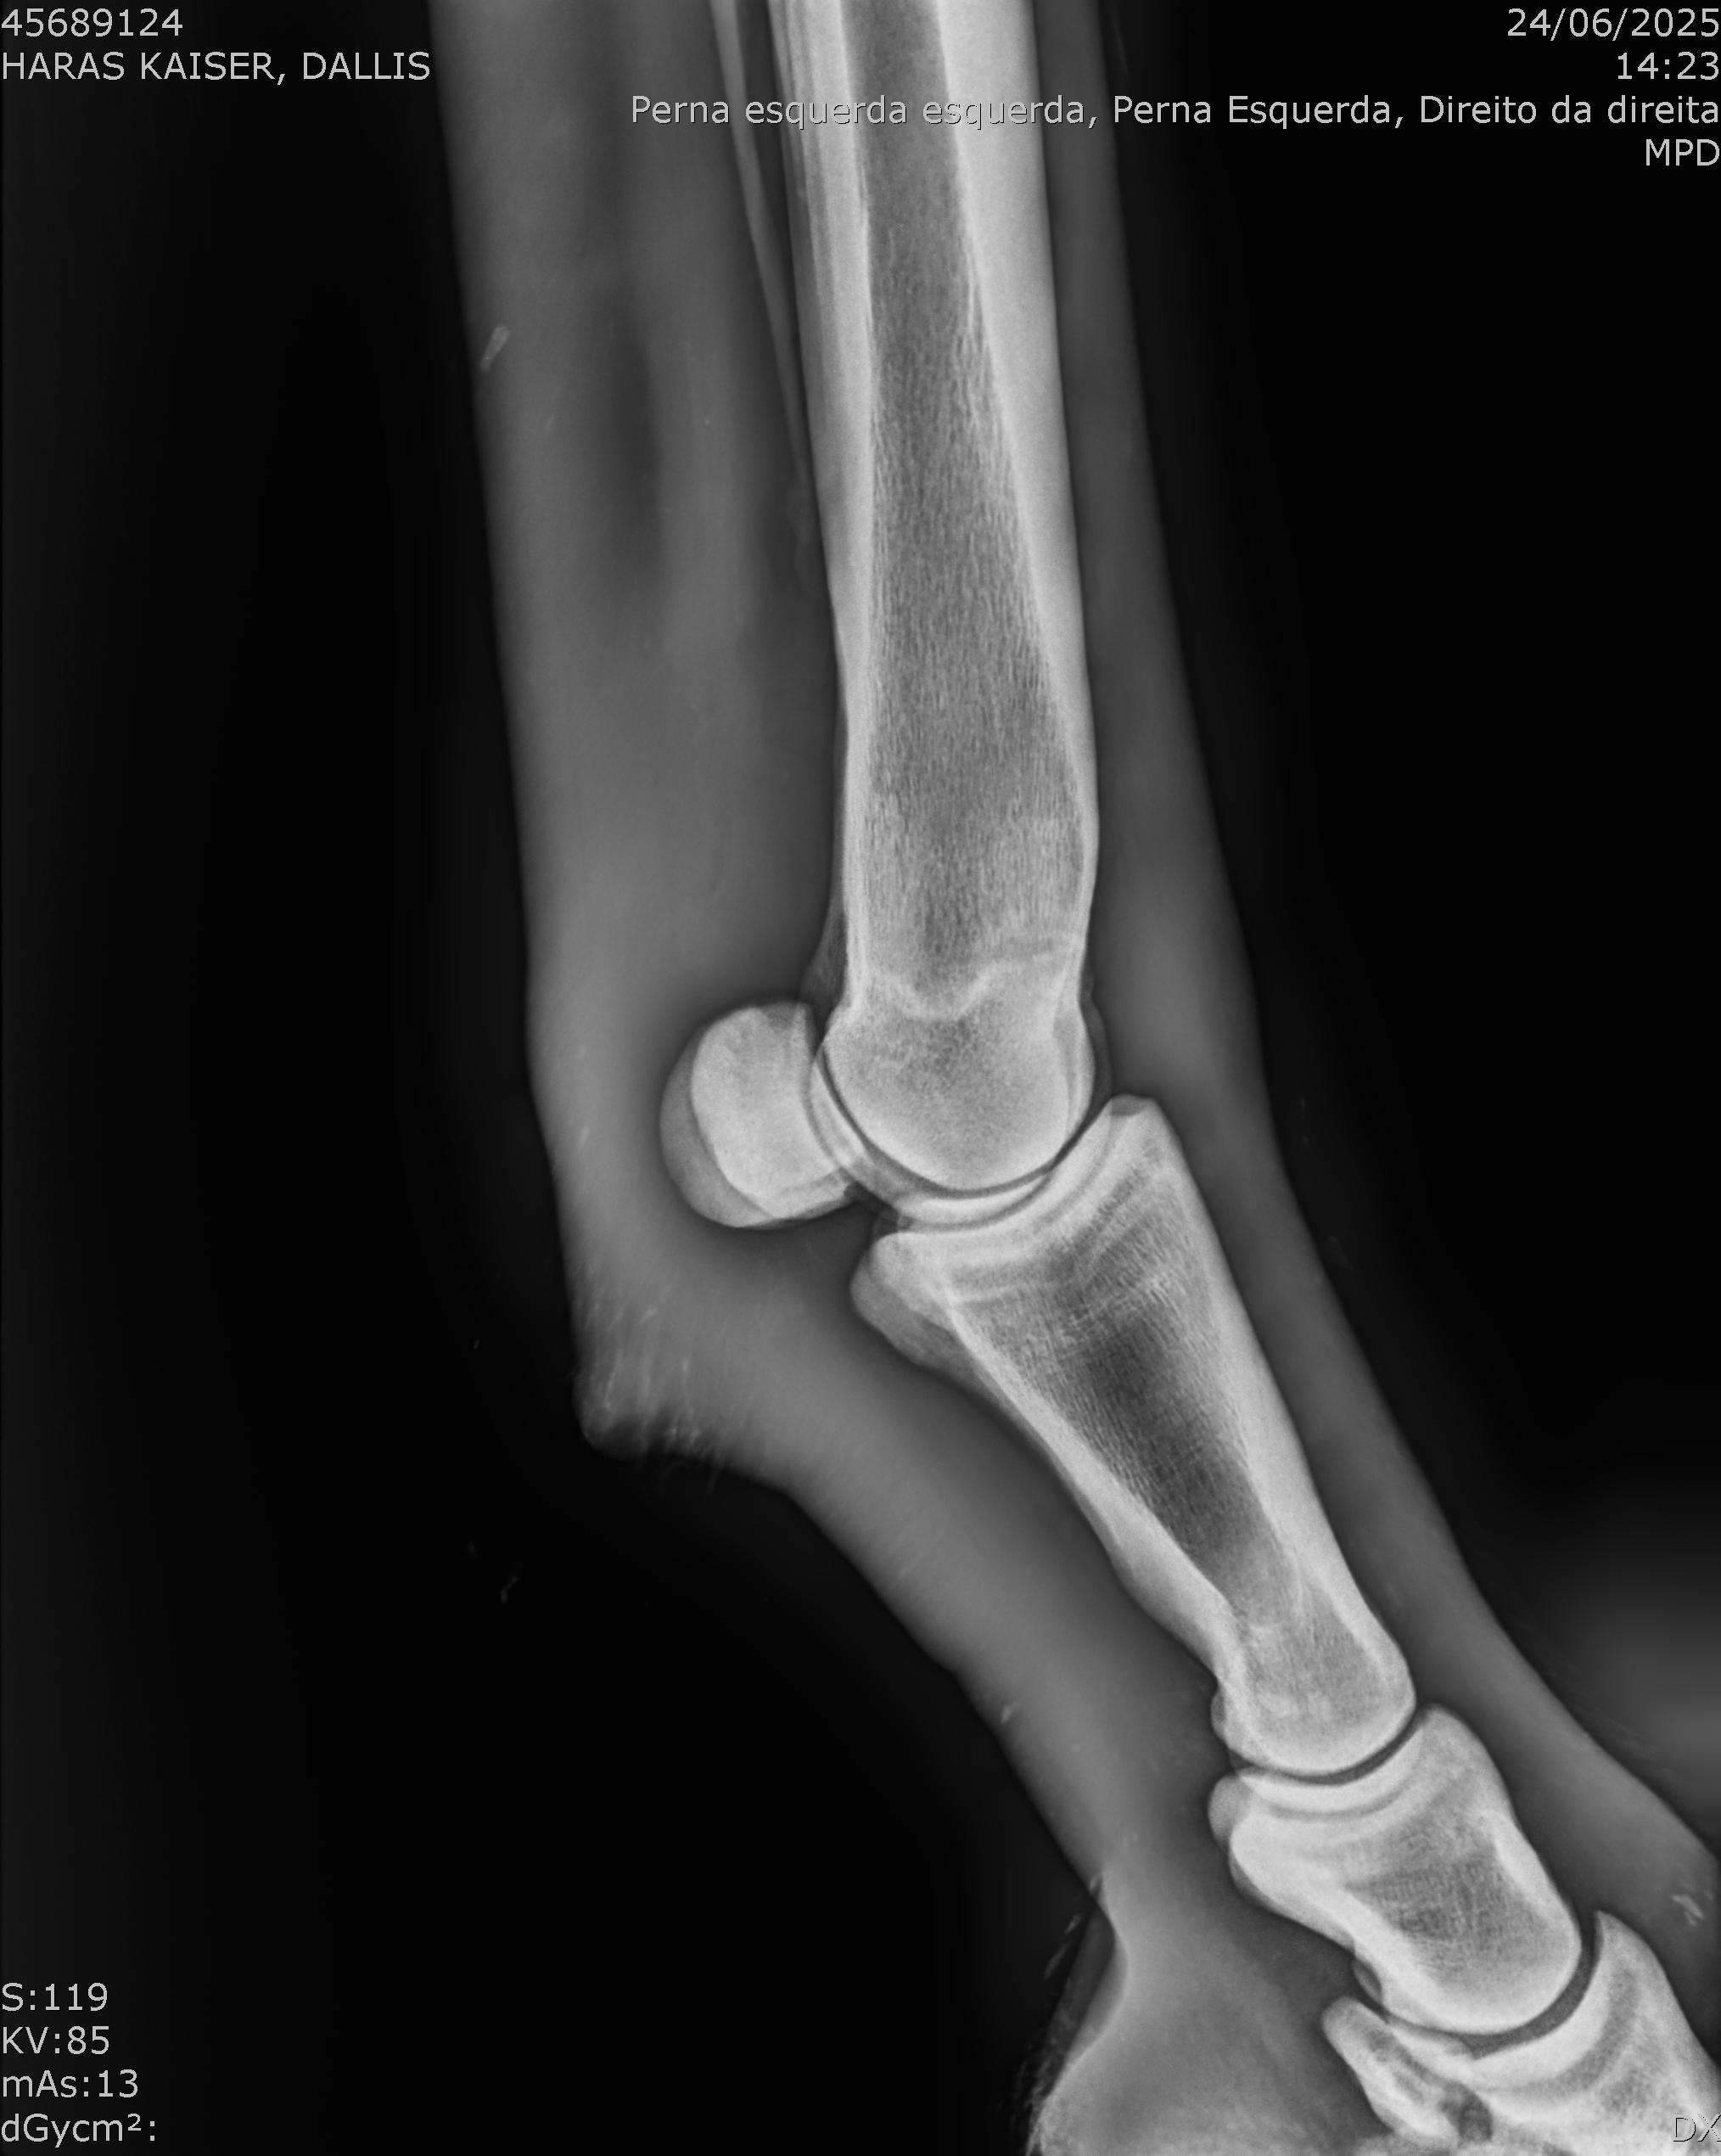

:: RAIOS-X DO LOTE